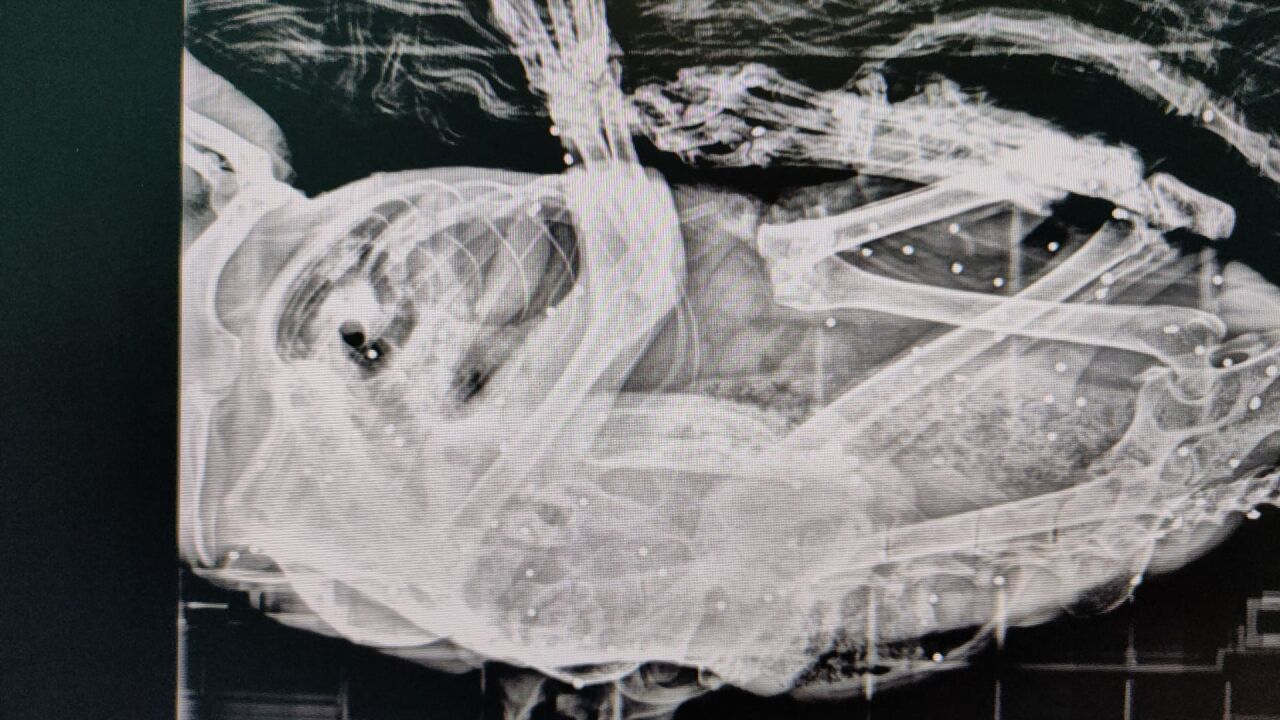

Hallan en Polanco un gato con más de 50 perdigones en su cuerpo | DEAN Cantabria

La asociación Gatucos Torrelavega ha atendido recientemente a un gato procedente de una colonia felina de Posadillo (Polanco) que albergaba más de 50 perdigones en su cuerpo. Se trata de Van Gogh, un animal que había sido intervenido quirúrgicamente por un carcinoma en la oreja y se encontraba recuperándose en el refugio cuando comenzó a mostrar cojera persistente. Tras su traslado al veterinario y la realización de pruebas radiológicas, se detectaron los perdigones en su interior.